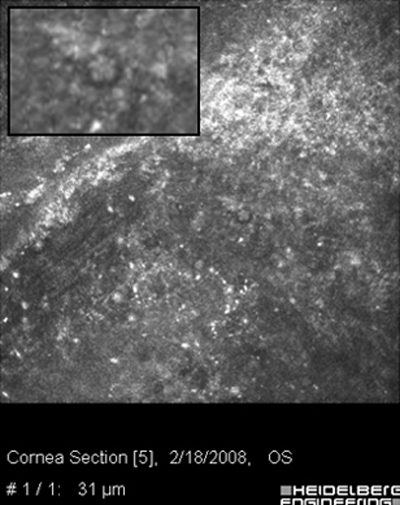

Ante la sospecha por los antecedentes e imágenes biomicroscópicas de una queratitis por Acantamoeba, debe hacerse su confirmación diagnóstica mediante extendidos de la superficie corneal para estudio microscópico, con las imágenes obtenidas “in vivo” con microscopía confocal (Figura 31 y 32) y mediante cultivos del parásito.

Fig. 31 Microscopía Confocal

Fig. 32 Comparar con quiste Acanthamoeba Fig 39

La positividad por la presencia de Acanthamoebas en uno o más estos estudios, asociada a las imágenes clínicas, confirma la etiología de la queratitis e indican la conducta terapéutica a seguir.